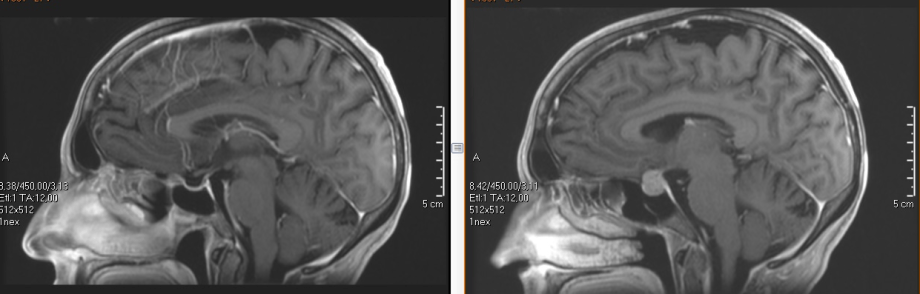

جراحة الغدة النخامية

تم معالجة الآفات النخامية بشكل كلاسيكي من خلال شقوق تحت اللسان ومجهر جراحي. في السنوات الأخيرة ، تم تطوير تقنيات التنظير الداخلي التي توفر ميزتان رئيسيتان: تسمح باستخدام الخياشيم الطبيعية ، وتجنب أي شق والحفاظ على الغشاء المخاطي للأنف بشكل أفضل ، وتوفر رؤية أقرب وأكثر حدة للمنطقة من خلال القدرة على إدخال البصريات إلى ثدي الورم. تتحول هاتان الميزتان إلى المريض في فترة ما بعد الجراحة

فريقنا رائد في إدخال تقنيات التنظير الداخلي لعلاج آفات سيلار بنتائج ممتازة.